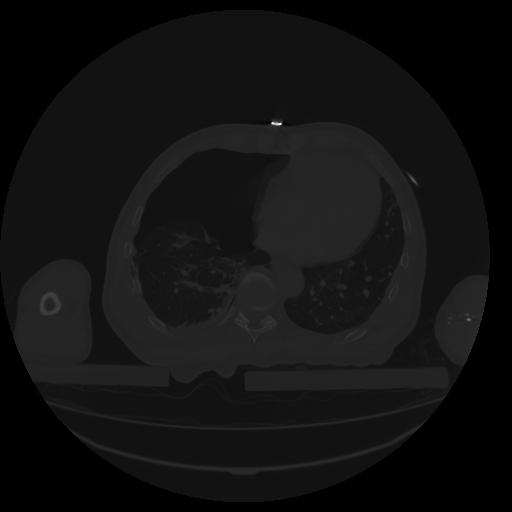

34 CUERPO,CE,Vol,1.0,CUERPO,,